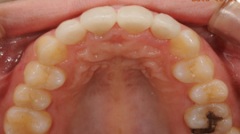

審美的治療の実例

出っ 歯が気になって来院した患者様です。海外に行くことが決まっていたので、矯正治療をするだけの時間の余裕がありませんでした。そこで、上の前歯4本をオー ルセラミッククラウンに変えました。いかがですか?どれが人口の歯か見分けがつきません。患者様ご本人も大満足してくださいました。

当院では咬み合わせ、歯列のみならず、歯肉との調和も考慮し治療にあたります。自然さを追求し、治療した後も結果を長く安定させるように、しっかりとメインテナンスサポート致します。

| Before | After |